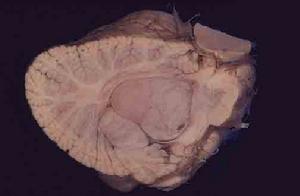

DNA病理學表現

1.室管膜瘤多位於腦室內,少部分可位於腦實質內及橋小腦角。腫瘤呈紅色,分葉狀,質地脆,血供一般較為豐富,邊界清。幕上腦室內腫瘤基底較寬呈灰紅色,有時有囊變。光鏡下室管膜瘤形態不完全一致,細胞中度增殖,核大,呈圓形或橢圓形,核分裂象少見,可有鈣化或壞死。低倍鏡下腫瘤切面如“豹皮”樣,為室管膜瘤診斷性標誌之一。高倍鏡下室管膜瘤有兩種結構特徵:其一為由腫瘤細胞按突起的方向向腫瘤血管壁排列所形成的“柵欄樣”結構,稱為“假玫瑰花”結節,其中央血管周圍為由長而內含膠質纖維的細胞突起所構成的無核區,外周由腫瘤細胞核所緊密圍繞;另一為室管膜瘤所特有的所謂“真室管膜玫瑰花”結節。此結構整體看較“假玫瑰花”小並少見,但對室管膜瘤有診斷價值。“真室管膜玫瑰花”結構由少量形態一致的多角腫瘤細胞放射狀排列所成,中央形成一管腔。免疫組化染色可見GFAP、維蒙亭(vimentin)及纖維結合素(fibronectin)等呈陽性。2.間變性室管膜瘤分別占幕上與幕下室管膜細胞腫瘤的45%-47%與15%-17%,又稱惡性室管膜瘤。鏡下可見腫瘤細胞增殖明顯,形態多樣,細胞核不典型,核內染色質豐富,分裂象多見。腫瘤喪失室管膜上皮細胞的排列結構,腫瘤內間質排列紊亂,血管增殖明顯,可出現壞死。間變性室管膜瘤易出現腫瘤細胞腦脊液播散並種植,其發生率為8.4%,幕下腫瘤更高達13%-15.7%。

3.室管膜下室管膜瘤多位於腦室系統內,邊界清楚,除位於腦室內者,尚可生長於透明隔、導水管及脊髓中央管內。腫瘤常有一血管蒂與腦幹或腦室壁相連。光鏡下表現為腫瘤細胞水腫,內含緻密的纖維基質與膠質纖維。瘤細胞核為橢圓形,染色質點狀分布,核分裂象極少。部分瘤內可有鈣化或囊變。室管膜下室管膜瘤內未見有星形細胞存在,可與室管膜下巨細胞型星形膠質瘤鑑別。